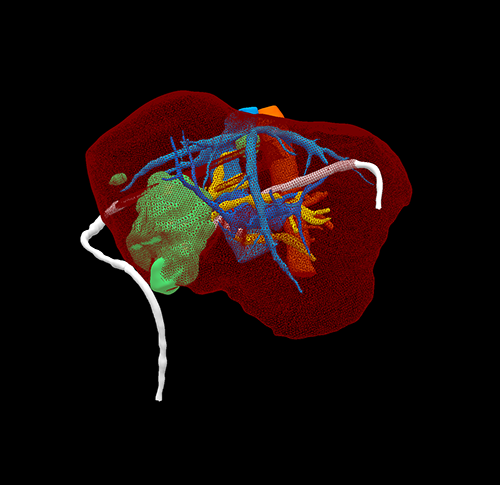

右肝胆管细胞癌、胆道梗阻---右三肝切除、左肝管空肠Roux-en-Y切除